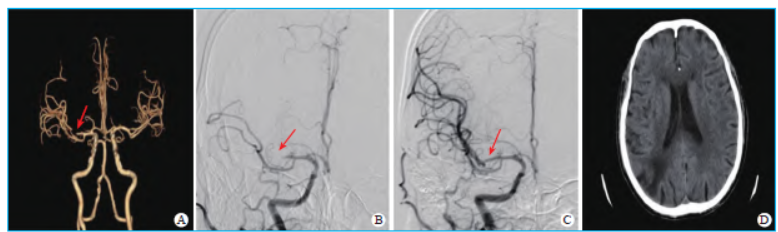

血管造影检查显示右侧大脑中动脉M1 段远端闭塞,左侧椎动脉V4 段中度狭窄,右侧椎动脉V4 段重度狭窄(图1)。请神经介入科医师会诊评估手术指征,诊断考虑“LVAD 植入术后急性缺血性脑卒中,右侧大脑中动脉M1 段闭塞”,拟行机械取栓治疗。

提示右侧大脑中动脉M1 段重度狭窄,泥鳅导丝、5F MPA1 导管及6FIntroSky 导管鞘采用同轴技术,超选右侧颈总动脉,将长鞘置于右侧颈总动脉分叉部近端,Sofia中间导管超选至右侧大脑中动脉M1 段分叉部近端,20 ml 注射器负压抽吸,抽出米粒大小血栓1枚,质韧、半透明、黄白色、长度约3 mm,术后立即进行脑数字减影血管造影,提示右侧大脑中动脉M1 段远端血管显影良好,完全再通,术后24 h复查头颅CT 未见新发梗死灶(图1)。

术后病理学结果显示,血小板聚集成小梁状,小梁之间充满大量凝固的纤维蛋白,边缘可见淋巴细胞与中性粒细胞点状浸润。复查头颅计算机体层摄影血管造影显示右侧大脑中动脉完全再通,无明显狭窄,左侧椎动脉V4 段中度狭窄,右侧椎动脉V4 段重度狭窄。患者神经功能障碍显著改善,美国国立卫生研究院卒中量表评分0 分。术后90 d 随访,患者的改良Rankin 量表评分为0 分,预后良好。

图1 计算机体层摄影血管造影、脑数字减影血管造影、头颅CT 检查结果 A. 术前计算机体层摄影血管造影;B. 术中脑数字减影血管造影;C. 术后脑数字减影血管造影;D. 术后24 h 头颅CT 检查。